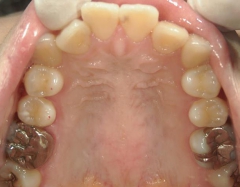

矯正歯科 治療前